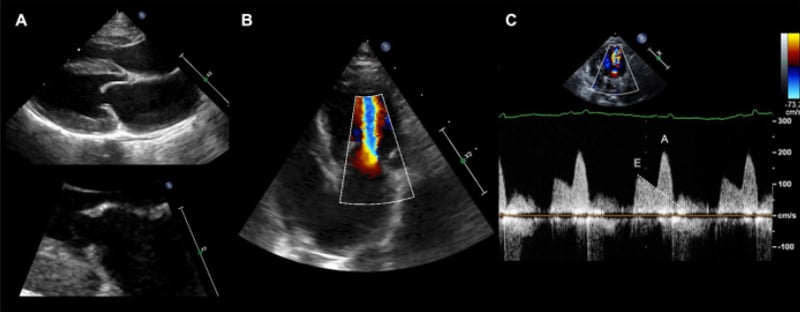

CardiovascularCardiovascular

UltrasoundUltrasound